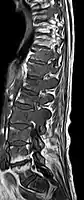

Avec l'IRM, on peut en particulier obtenir de bonnes images des tissus mous. C'est un processus idéal pour le diagnostic des métastases spinales (métastases des vertèbres). Avec l'IRM, on peut en outre rendre visible des complications supplémentaires dans la région des métastases spinales, comme des infections ou des blessures des tendons et ligaments, des œdèmes de la moelle osseuse après une fracture récente[120],[121], ou la compression de structures nerveuses[18]p. 16. Au moyen de séquences STIR, il est possible d'évaluer l'âge d'une fracture. Pour la détection des métastases, la pondération T1 avec des produits de contraste au gadolinium, comme l'acide gadotérique est particulièrement bien adaptée. Le produit de contraste s'accumule particulièrement fort dans les métastases[18],[122].

- Comparaison scanner/IRM pour des métastases ostéolytique d'un cancer du sein dans la colonne vertébrale

Scanner sagittal reconstruit, représentation dans la fenêtre osseuse. Comme la patiente avait des métastases dans toutes les régions du corps, elle ne pouvait pas lever les bras pour l'examen, ce pourquoi les mains sont présentées.

Scanner sagittale, parties molles. Outre les métastases dans la colonne vertébrale, qui envahissent en partie le canal médullaire vers l'arrière, métastases aussi dans le sternum. Plus des métastases dans le foie.

IRM natif avec pondération T1.

IRM sagittal natif avec pondération T1. On voit clairement l’extension jusqu'aux lames vertébrales.